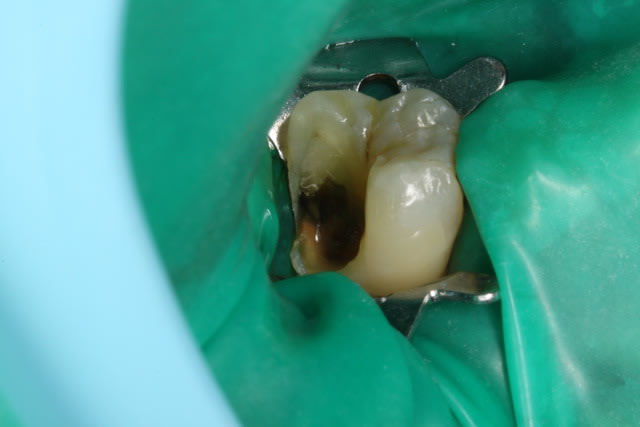

Un petit onlay du dimanche dernier qui m'a fait plaisir. A souligner le travail du prothésiste, content de son boulot après avoir vu les photos.

Pour Sethef: la digue (medium) ne m'a pas gêné, mais le premier clamp que j'ai voulu mettre remontait partiellement sur la limite.

La cavité d'accès pour une dévit est insuffisante , la dent est vivante . La limite de la cavité est sus gingivale .

Dent vitale. Il y avait un compo OD et le pan V a lâcher. Limite supra-gingivale.

Ci joint une autre vue.